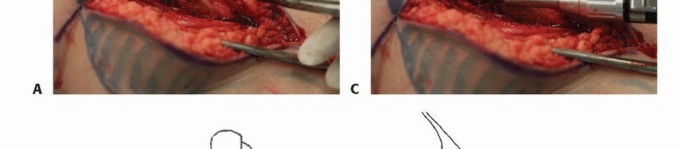

الكشط والعلاج المساعد (Curettage and Adjuvant Therapy):

تُستخدم عادة لأورام العظام الحميدة، حيث يتم كشط الورم من داخل العظم، ثم يتم استخدام مواد مساعدة مثل الفينول أو النيتروجين السائل أو الكي الكهربائي لتدمير أي خلايا ورمية متبقية.

5. العلاج بالتبريد (Cryoablation): النهج الثوري

يُعد العلاج بالتبريد، خاصةً بتقنية الصب المباشر بالنيتروجين السائل، ثورة حقيقية في علاج أورام العظام، حيث يقدم بديلاً فعالاً وآمنًا للجراحات الكبرى، مع الحفاظ على الطرف المصاب ووظيفته. يعتمد هذا النهج على تدمير الخلايا السرطانية عن طريق تعريضها لدرجات حرارة منخفضة جدًا، مما يؤدي إلى تجميدها وموتها.

آلية عمل العلاج بالتبريد:

تتمثل الفكرة الأساسية في تجميد الخلايا السرطانية وتذويبها بشكل متكرر. عند تجميد الخلايا، تتكون بلورات الثلج داخل وخارج الخلايا، مما يؤدي إلى:

تقنية الصب المباشر بالنيتروجين السائل: تفاصيل الإجراء

تعتبر تقنية الصب المباشر بالنيتروجين السائل (Direct Pouring Liquid Nitrogen Technique) في العلاج بالتبريد لأورام العظام من التقنيات المتقدمة التي تتطلب دقة عالية وخبرة جراحية متخصصة. يفضل الأستاذ الدكتور محمد هطيف هذه التقنية نظرًا لفعاليتها في تحقيق تجميد عميق وشامل للورم، مع الحفاظ على الأنسجة السليمة المحيطة.